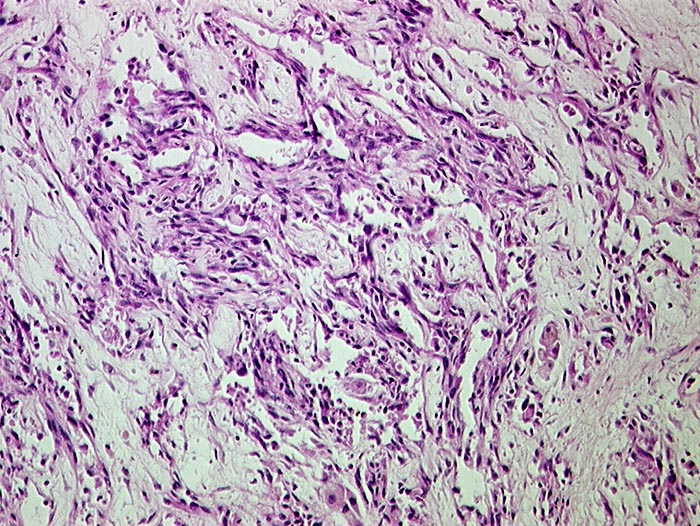

Angiosarkom der Leber

maligner Tumor

Pathologischer Befund